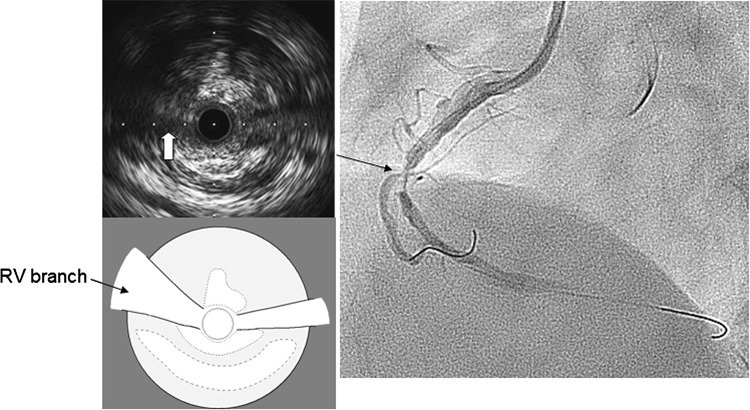

Fig. 1.

Angiogram and intravascular ultrasound (IVUS) image (Opticross; Boston scientific, Japan) at the right ventricular (RV) branch bifurcation after guidewire crossing and suction. IVUS image revealed that culprit lesion included attenuated plaque, and the RV branch was running through the plaque (white arrow). A small branch was also seen at the opposite side of RV branch by the angiogram and IVUS

Fig. 2.

Angiogram after stenting showed that the right ventricular (RV) branch remained completely occluded. Intravascular ultrasound image from the right coronary artery main vessel at the RV branch bifurcation revealed that the RV branch was detected at 9 o’clock position. The true lumen of the RV branch (white arrow) was collapsed by an expanded false lumen that was presented as a high echogenic lumen (white arrowhead)